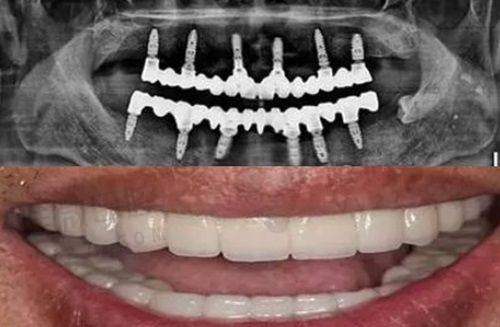

一、种植牙:进口品牌竟有"学生价"?

在阳泉市第一人民医院,种植牙价格体系就像"汽车品牌展厅":国产种植牙5500元起相当于经济型轿车,韩国登腾6000元起是性价比之王,而瑞士ITI12800元起则属于牙科界的"奔驰"。特别要划重点的是,同款瑞典诺贝尔种植体,这里15800元的价格比周边私立机构普遍低2000-3000元。科室采用的"种植体品牌分级报价"策略,让患者既能享受进口品质,又不必为品牌溢价买单。